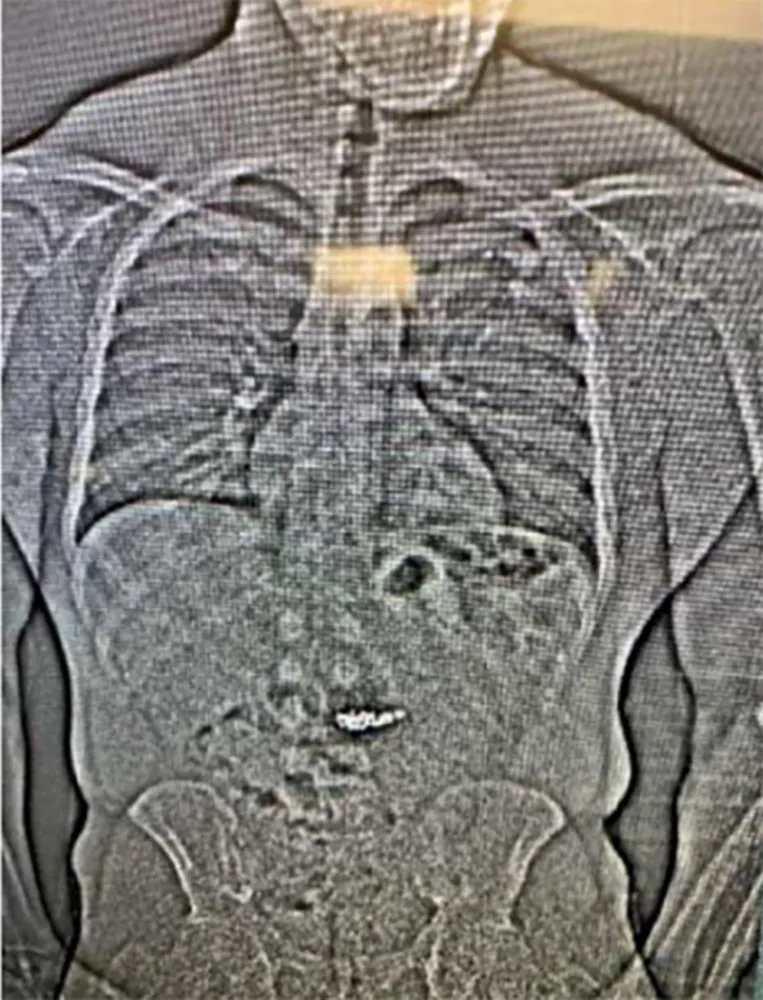

Subsequent to his escape, police tracked Gilder using mall security footage and identified his vehicle. He was apprehended on Interstate 10 after being pulled over for a traffic violation. A trooper reportedly overheard Gilder state, “I should have thrown them out the window,” as he was placed under arrest for resisting. Upon arriving at the Washington County Jail, authorities detected that he had swallowed several foreign objects, which are believed to be the stolen earrings, as confirmed by an X-ray revealed by BBC.